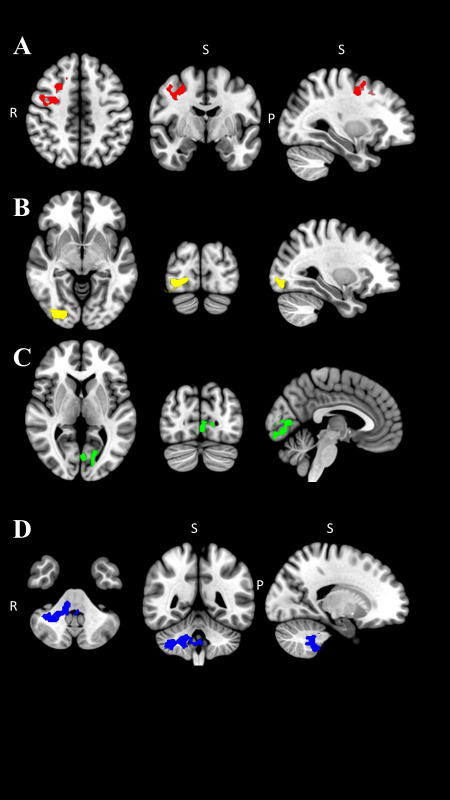

Sex Specific Brain Activations During Single Leg Exercise Published In International Journal 145360

Sex Specific Brain Activations During Single Leg Exercise Published In International Journal